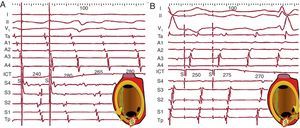

Figura 16. A: encarrilamiento de aleteo auricular típico (antihorario) por estimulación (S) del istmo cavotricuspídeo. La activación de la aurícula derecha anterior es descendente (Ta→A4) tanto en los ciclos estimulados como al detener la estimulación, demostrando que los frentes estimulados siguen el circuito. En cada ciclo se produce un segundo frente estimulado en dirección contraria al circuito (antidrómico) que colisiona con el frente encarrilado en el ciclo anterior (esquema). B: idéntico fenómeno con secuencia inversa en un aleteo auricular típico horario. La aurícula derecha septal muestra secuencia descendente (Tp-S4) durante el encarrilamiento, igual que tras la estimulación. El primer ciclo (retorno) tras la estimulación es igual que los ciclos espontáneos de aleteo auricular en los 2 casos y no se observa cambio de morfología en el electrocardiograma ni de secuencia en los electrogramas (encarrilamiento oculto, sin fusión), lo que es típico de un istmo estrecho del circuito de taquicardia auricular macrorreentrante. ICT: istmo cavotricuspídeo.

Cuando el patrón ECG es característico y no hay antecedentes de cirugía cardiaca, se acepta hacer ablación del ICT sin otra demostración del mecanismo del AA. En casos en que la morfología no es tan clara o la enfermedad asociada hacen posible la presencia de circuitos atípicos de TAMR, asociados o no al AA típico, resulta necesario el estudio electrofisiológico de la taquicardia clínica, ya sea espontánea o inducida durante el estudio por medio de estimulación basal o durante infusión de isoproterenol. Con un solo catéter-electrodo multipolar introducido desde la cava inferior, se puede demostrar la secuencia circular de activación de la AD y el catéter deflectable utilizado para la aplicación de radiofrecuencia registrará la activación en el ICT haciendo «puente» entre la activación de la AD anterior y AD septal bajas, sea cual sea la dirección de giro (Figura 16). Aunque la cartografía así obtenida sea muy expresiva, se recomienda demostrar la participación del ICT por medio de la estimulación del ICT, comprobando que el ciclo local tras estimulación es ≤ 20 ms más largo que el basal del AA. Durante el encarrilamiento del ICT se puede comprobar el mantenimiento de la activación circular en la mayor parte de la AD, lo que demuestra que los estímulos se están encarrilando en el circuito (Figura 16).